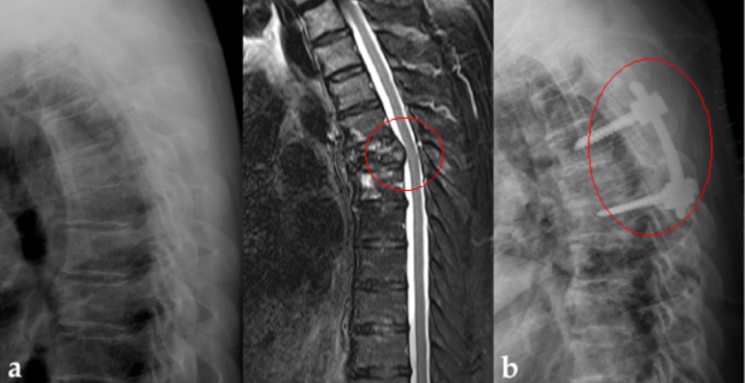

비소세포폐암이 척추로 전이되어 걷지 못했던 50대 환자의 X-ray와 MRI 검사 사진. (사진 제공=서울성모병원)